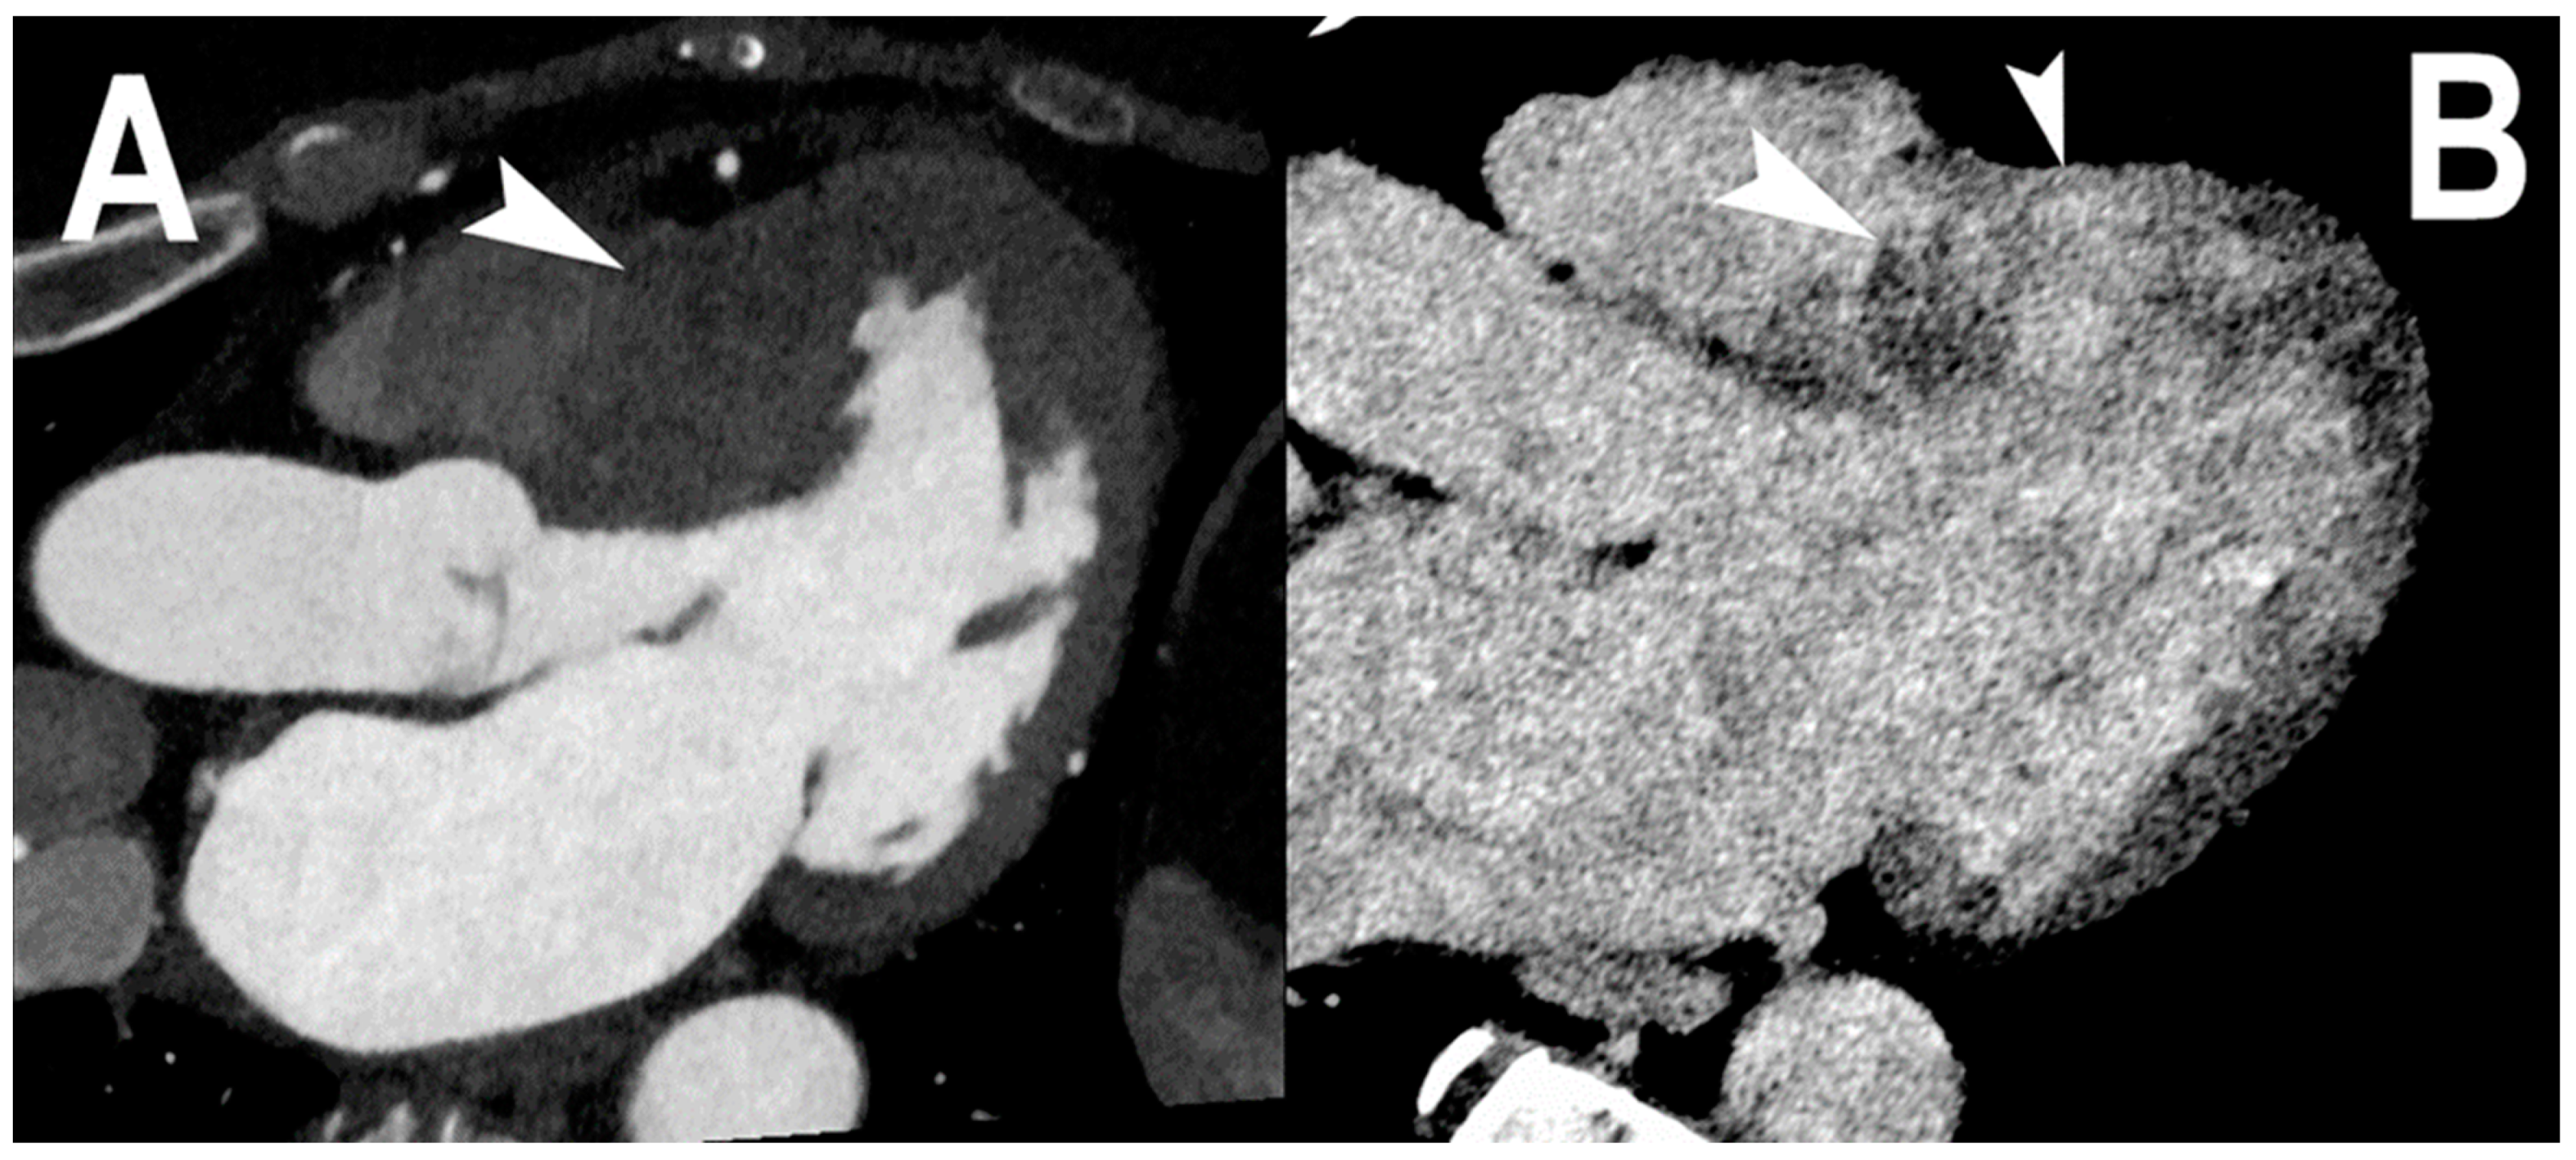

3.6. Myocardial Tissue Imaging

- Polacin, M.; Templin, C.; Manka, R.; Alkadhi, H. Photon-counting computed tomography for the diagnosis of myocardial infarction with non-obstructive coronary artery disease. Eur. Heart J. Case Rep. 2022, 6, ytac028. [Google Scholar] [CrossRef] [PubMed]

| Symons et al. [27] | 2017 | In vivo (canine) | 3 | Myocardial tissue characterization | The distribution and morphology of myocardial scar by PCCT single-energy and gadolinium map correlated well with MRI and histology. The gadolinium map had 31% higher contrast-to-noise ratio than the CT single-energy images for identifying infarct versus remote tissue. |

| Mergen et al. [39] | 2022 | In vivo (human) | 30 | Myocardial tissue characterization | With PCCT virtual mono-energetic and dual-energy-derived ECV quantification showed high correlation (r = 0.87, p < 0.001) with narrow limits of agreements and a mean error of 0.9%. |